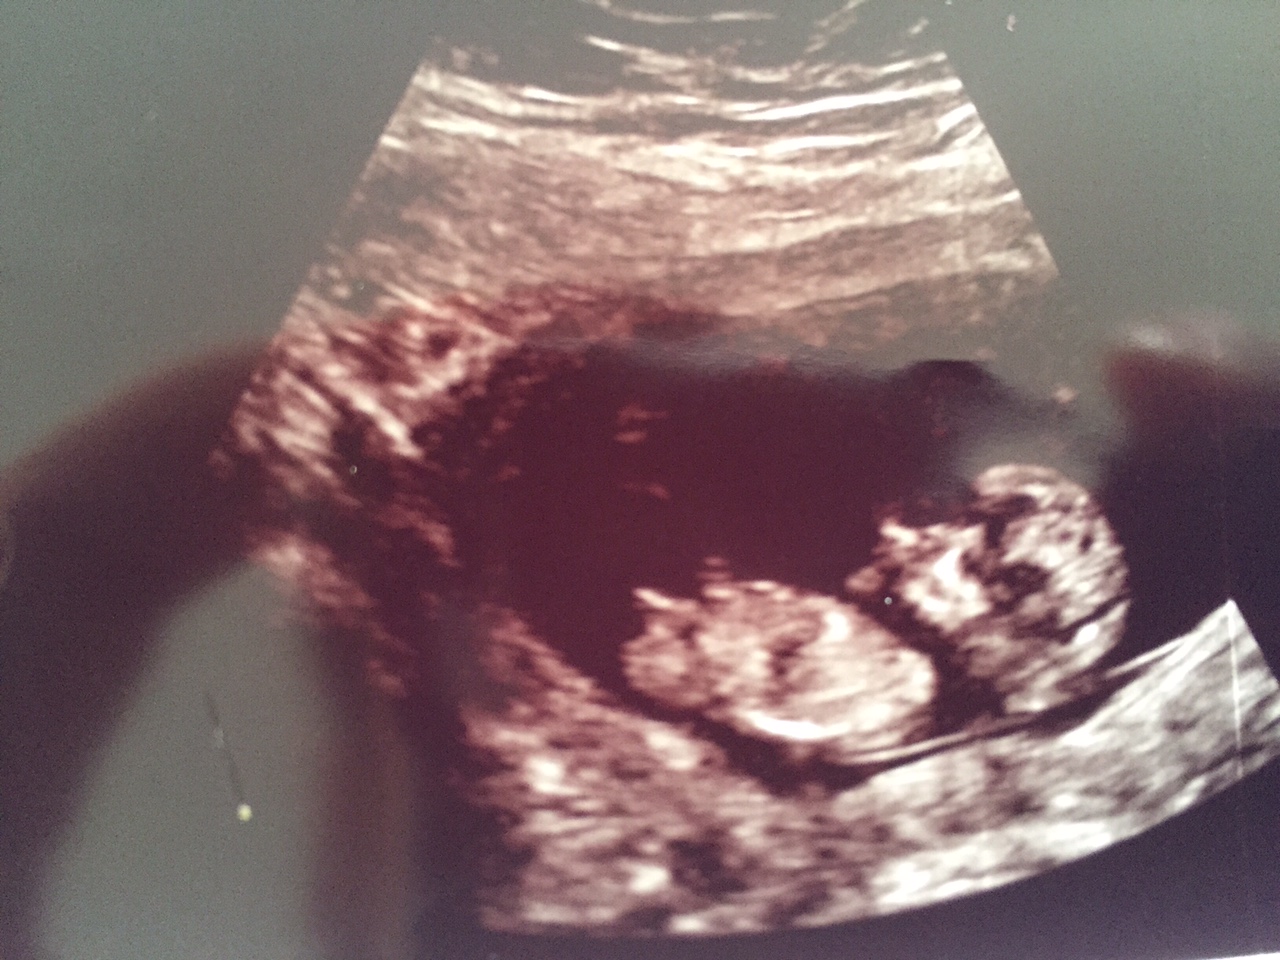

Hi everyone, I'm very curious what you all think. Boy or girl? This pics are taken at 12 weeks exactly

girl xx

early but girly

Looking girly

First picture is making me lean boy but the second is flat and girly

Maybe 12 weeks is a tad early